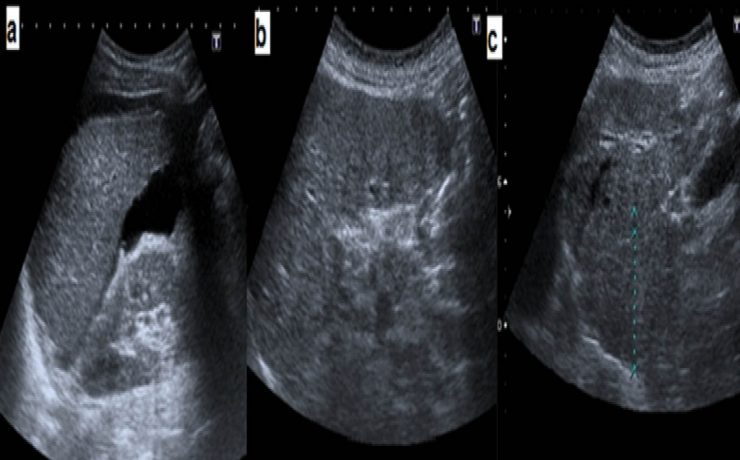

El incremento de la obesidad, del síndrome metabólico y su subsiguiente manifestación hepática, el hígado graso no alcohólico, se ha convertido en una enfermedad muy común en la práctica médica. El desarrollo de los conocimientos sobre el NASH se basa en la teoría inicial de los dos golpes o momentos.